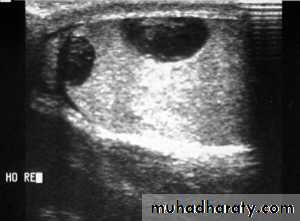

TORSION OF THE TESTIS ( Torsion of spermatic cord)

Rotation of the testis around the vertical axis of the cordIt is time limited due to arterial obstruction & the patient might lose his testis by ischemia (gangrene) if the diagnosis is delayed (6 hours).

Doppler ultrasound scan will confirm the absence of the blood supply to the affected testisTreatment